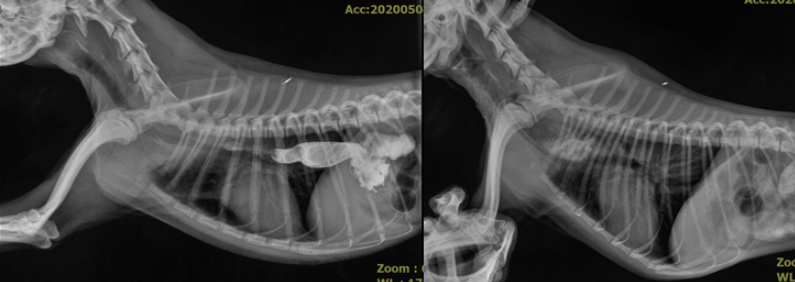

구토의 원인을 확인하기 위한 여러 검사 중, 방사선 촬영에서 액상의 물질은 식도를 잘 통과하나 고형의 음식을 먹이니 심장 위쪽에서 막혀 더 이상 내려가지 못하고 토출을 하는 것이 관찰되었습니다.

방사선 촬영 상 관찰된 식도의 이상을 확인하기 위하여 내시경 검사를 진행하였고 내시경 검사상 식도의 협착 확인되었습니다.

식도는 매우 비좁아져 있어 1cm가 안되는 내시경 조차 통과할 수 없었습니다.